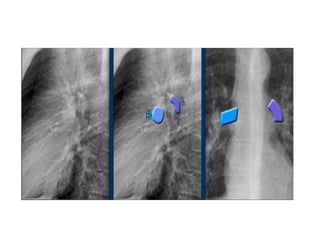

Pulmonary vessels

• the right pulmonary artery runs in front of the right

main bronchus, which is usually lower in position than

the left main bronchus. While the left pulmonary

artery runs over the left main bronchus,

• Hence the right hilum is lower than the left.

Only in a minority of cases the right hilus is at the same

level as the left, but never higher.

• the right pulmonary artery (in blue) which passes in

front of the right main bronchus and is lower than the

left main pulmonary artery (in purple) passes over the

left main bronchus.

Pulmonary vessels • theright pulmonary artery runs in front of the right main bronchus, which is usually lower in position than the left main bronchus. While the left pulmonary artery runs over the left main bronchus, • Hence the right hilum is lower than the left. Only in a minority of cases the right hilus is at the same level as the left, but never higher. • the right pulmonary artery (in blue) which passes in front of the right main bronchus and is lower than the left main pulmonary artery (in purple) passes over the left main bronchus.